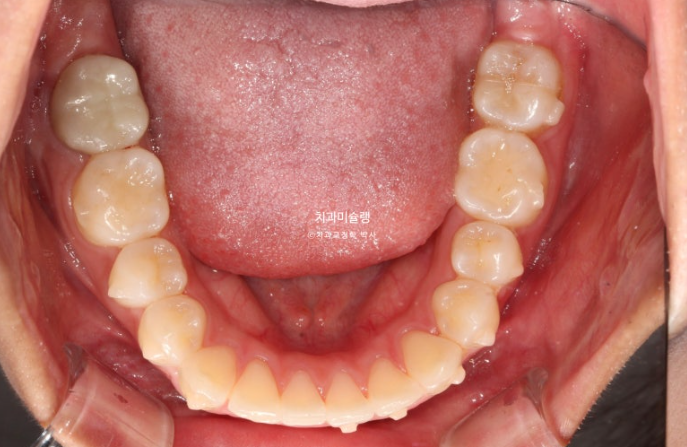

치료시작 11개월 차, 첫 세트의 48개 장치를 모두 낀 후 모습입니다.

중심선이 아직 약간 어긋나 있지만 덧니와 개방교합은 개선되었습니다.

좌측의 2급 교합이 아직 남아있습니다.

이 부분을 개선하고자 추가장치 제작에 들어갑니다.

재제작 추가장치 갯수는 10개입니다.

다시 약 4개월치 장치를 챙겨서 출국, 가을학기동안 열심히 껴줍니다.